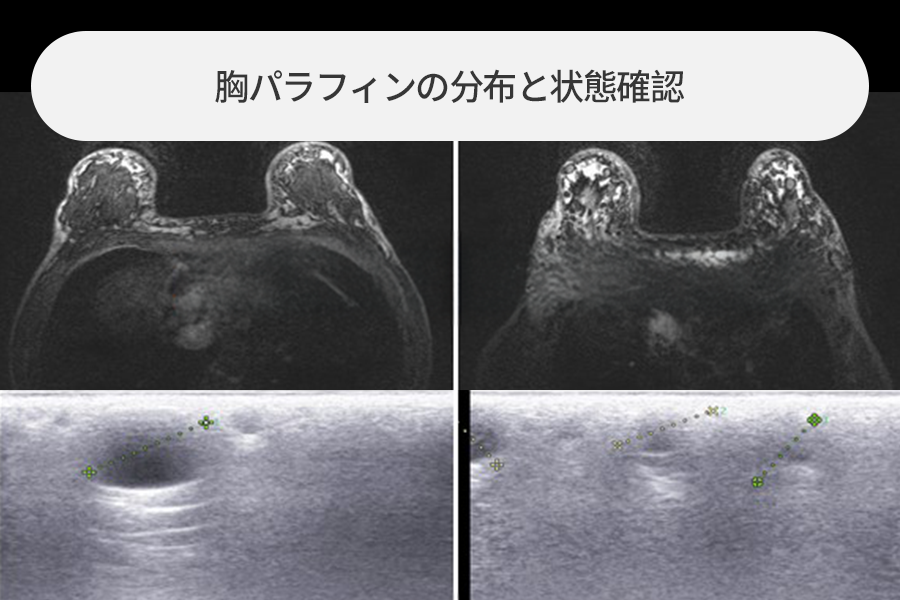

乳房パラフィン除去とバスト挙上、インプラント拡大を同時に行った場合

乳房に「コラーゲン注射」を打ったとおっしゃる方で、ずきずきする乳房痛があり来院されました。

可能であれば垂れたバストの矯正とボリューム拡大も希望され、全体的な検査の結果、

パラフィン除去と垂れたバストの挙上、インプラント拡大が可能な状態であったため、同時手術を行った事例です。